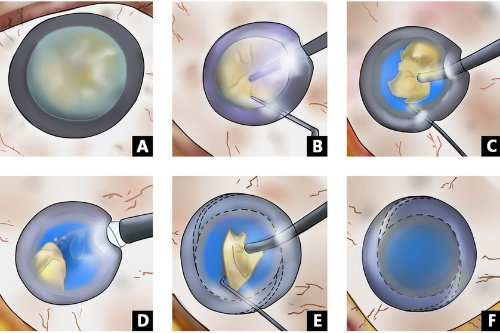

家人们,我做白内障三焦晶体植入手术已经有一段时间啦,现在来给大家好好分享下我1个月和6个月的真实感受,真的就像告别了“毛玻璃”国内外,重见清晰光明!

我都忍不住感叹,这三焦晶体植入手术简直就是我的救星,让我重新找回了清晰的视野。

家人们,如果你们也被白内障困扰,不妨考虑考虑三焦晶体植入手术。相信我,就像我一样,告别“毛玻璃”国内外,开启清晰、多彩的新生活!